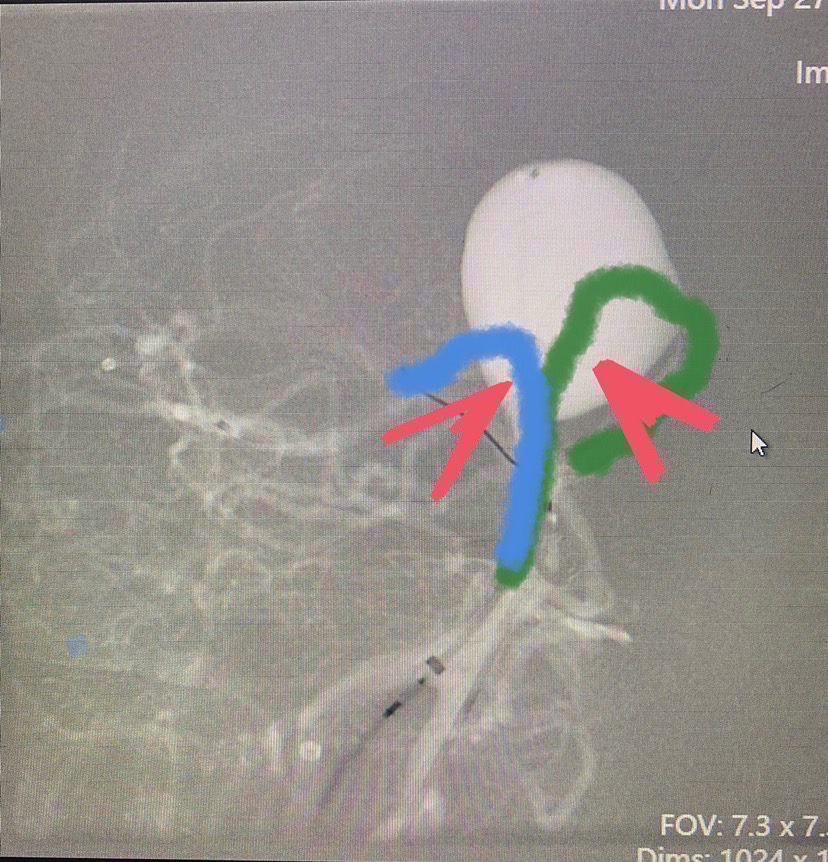

上个示意图说明一下:蓝绿线条表示支架形态,两个红箭头表示弹簧圈无法致密填塞的部位。

那么改变一下思路,将绿色的普通支架换成血流导向装置,蓝色普通支架呈T形放置,瘤腔内疏松填圈,理论上似乎更为合理。如示意图(画图水平超烂,见谅)。